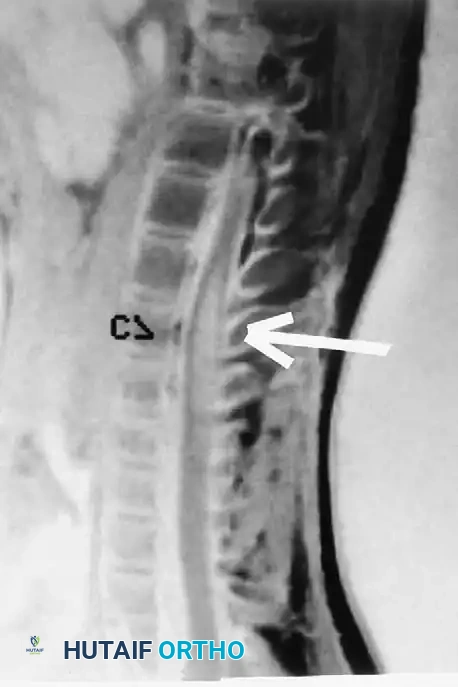

Associated Surgical & Radiographic Imaging

Hutaifortho's Orthopaedic Diagram